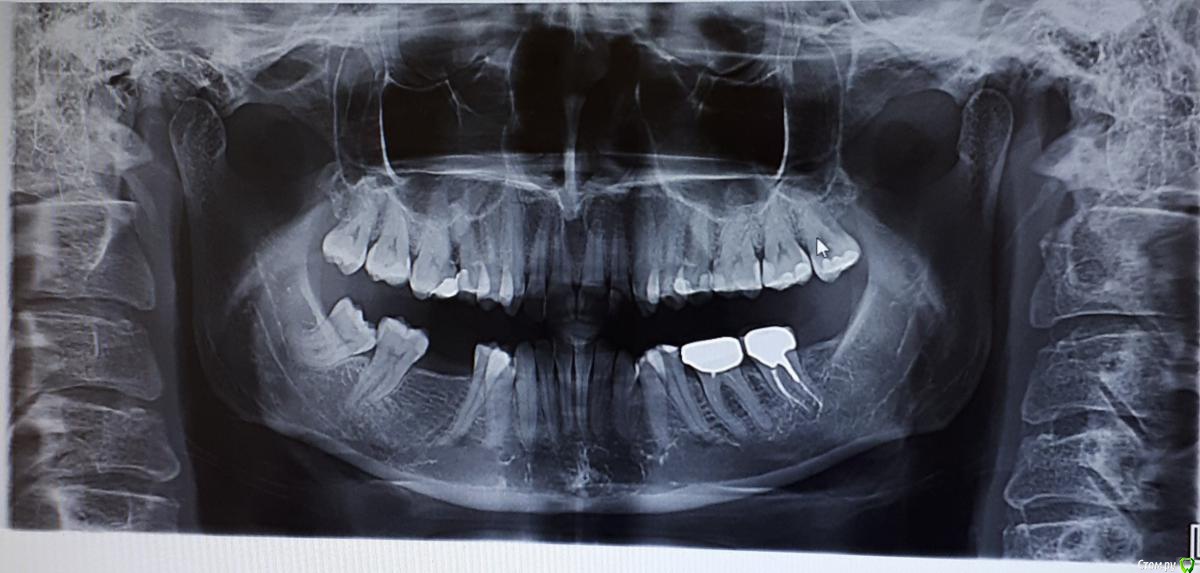

Thunder Опубликовано 17 октября, 2019 Поделиться Опубликовано 17 октября, 2019 Приветствую всехПрошу быть снисходительными: рассказываю свою историю первый раз, заранее приношу извинения за возможный сумбур и некорректность в использовании проф. терминологии. Мне 40 лет. У меня:-глубокий прикус-скученность зубов во фронтальном отделе в/ч и н/ч; -короткая уздечка верхней губы, -мелкое преддверие полости рта, -тонкий биотип пародонта; -проблемы с суставом (левым), который периодически дает о себе знать: обычно ограничивается щелканьем, но пару раз и воспалялся (боли, рот с трудом открывался, особенно по утрам). Ничего, кроме местных мазей на сустав не наносила и особенно им никогда не занималась.- В этом году мне поставили диагноз полиостеоартроз (болят суставы нижних конечностей). - постепенно появился перекос челюсти влево, видно уже невооруженным глазом (возможно, после удаления верхней левой восьмерки)Прикус никогда не исправляла, по разным причинам, в том числе, потому что не хотела ставить брекеты. И сейчас не хочу (комплексы). Комплексы от некрасивой улыбки тоже были, но к своей внешности за столько лет уже привыкла (и смирилась), кроме того она мне совершенно не мешала жить. Однако!В последние годы вынесла основную мысль от стоматологов – мои суставы разрушаются (в большей степени левый), происходит это из-за моего прикуса, который срочно надо исправлять. Эстетика лица для меня – вторична. Вся работа над зубами должна проводиться именно для сохранения сустава (ну и чтобы зубы не потерять).В начале 2019 г. были сделаны ОПТГ, КТ и ТРГ. Есть еще зонография ВНЧС (правда от 2017г.) // не поняла, как КТ подгрузить, но есть описание врача Пикассо. Если надо будет, просто загружу как текст. Остальные фото, надеюсь, подгрузить получится// По КТ ортодонт, к которому я, наконец, обратилась, выявил «убыль костной ткани межальвеолярных гребней и вестибулооральных стенок по смешаному типу до 2,0 мм.» (кортикальная пластинка истончена по вестибулярной поверхности на передних зубах (в/ч зубы 1.2-1.1,2.1-2.4; н/ч зубы 3.1.-3.4, 4.1-4.5) до 0,1 мм). Мой ортодонт (лечение на капах) сказала, что риск потерять зубы при лечении на капах – 50/50, при лечении на брекетах – и того выше. После этого, конечно, я ушла.Стала искать дальше. Каждый раз мнения разнились:1 вариант: можно капами исправить прикус, но крайне осторожно2 вариант: только (!) брекеты. Тема потери зубов обходится стороной или уверяют, чтобы зубы останутся на месте засчет длинных корней. Если я не поставлю брекеты притом срочно – через несколько лет я потеряю все зубы, и мне придется тратиться на съемные протезы3 вариант: зубы вообще не трогать, просто всю жизнь носить каппу, помогающую моему суставу.4 вариант (стоит особняком): суставная каппа на нижнюю челюсть + одновременно аппарат ALF на верхнюю.Почему ALF? потому что из всех ортодонтических аппаратов для исправления прикуса этот – самый щадящий. Брекеты категорически не рекомендованы, потому что самые агрессивные по воздействию, каппы дороже + отмели из-за сустава: его было удобнее лечить параллельно с ALF. Смысл использования у меня ALF (как поняла) не столько в расширении челюсти, сколь в изменении наклона верхних зубов, которые не «пускают» нижнюю челюсть вперед. Мои зубы при этом не выпадут, а врастут в кость, изменив угол наклона.Второй этап – ALF или инвизилайн на нижнюю челюсть; и для возобновления смыкания боковых зубов – пломбы или коронки (эта часть смутила). В данном лечебном плане было прекрасно все, кроме моей неуверенности в достаточной квалификации врача. У меня сложилось впечатление, что для врача эта методика как бы.. далеко не основная. Она использует ALF просто как один из вариантов ортодонтических аппаратов (наряду с брекетами и пр.), а я так понимаю, у ALF философия немного другая (тесная связь с осанкой, остеопатией и пр.) – хотя могу и ошибаться. И в принципе эта методика новая, не особенно опробованная в России, отзывов нет, особенного опыта у врачей тоже. Страшно.Мучают вопросы, на которые здесь, возможно, получу ответы:1. мне были рекомендованы френулопластика на в/ч, вестибулопластика на н/ч. На сколько это необходимо в моем случае и что будет, если я их делать не буду2. последний ортодонт мне пригрозил полной потерей зубов через некоторое время, если не поставлю брекеты. Она была единственной, кто мне озвучил подобные последствия. Альтернативой исправления прикуса действительно будет только полное протезирование через несколько лет? если я не буду делать ничего, то чем, на самом деле это грозит? 3. какие ортодонтические аппараты при моих лежащих на поверхности зубах мне рекомендованы? не потеряю ли я зубы в результате лечения?страшно! 4. ваше мнение об ALF!5. в продолжение 3-го вопроса: возможно ли (при варианте «брекеты») мое лечение на лингвальных брекетах? можно в комбинированном варианте: в/ч лингвальные + н/ч обычные вестибулярные? готова терпеть все неудобства с ними связанные. но "внешние" брекеты не хочу, не могу психологически заставить себя носить. 6. так понимаю, что, учитывая мой диагноз полиостеоартроз и проблемы с суставом – о нем я тоже не должна забывать. И должна лечиться у врача, который эти проблемы (и все остальные) умеет учитывать. В общем, хотелось бы услышать ваши рекомендации по поводу врача в Москве. Можно в личку Заранее спасибо! Ссылка на комментарий